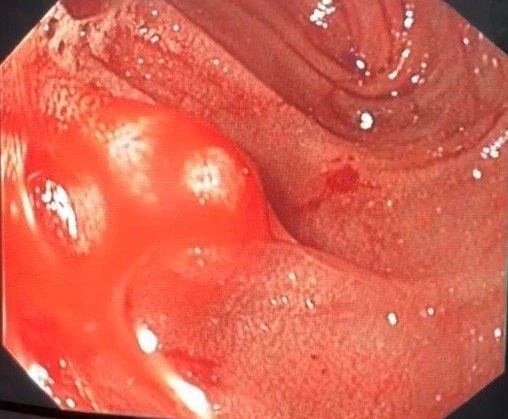

Hình ảnh nội soi đoạn ruột non đang xuất huyết của bệnh nhân. Ảnh: BVCC

Qua thiết bị này, các bác sĩ chẩn đoán vị trí chảy máu xuất phát từ nhánh nhỏ của động mạch mạc treo tràng trên tương ứng với đoạn hỗng tràng (ruột non) hay còn gọi là xuất huyết Dieulafoy. Do đó, các bác sĩ quyết định phẫu thuật kết hợp nội soi ruột non trong lúc mổ, cắt đoạn ruột non có sang thương xuất huyết Dieulafoy.